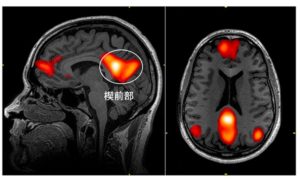

下の図は、スキーマの獲得に関わる脳領域について図示したものですが、

脳の中でも、意味処理に関わる側頭葉の前部領域、様々な感覚情報の統合に関わる頭頂葉の角回、意思決定に関わる腹側内側前頭前野がスキーマの獲得に関わっていることが示されています。

側頭葉というのは意味処理に関わる領域なのですが、

側頭葉でも前に方に行けば行くほど、抽象度の高い意味情報(例えば、愛や正義、悪などの意味)の処理に関わるとされています。

スキーマの理解に際しては、この深い意味を処理する側頭葉の前の方の領域が活動することが示されています。

また頭頂葉は一般に様々な感覚情報がまとめられる領域なのですが、その頭頂葉の中でも角回というのは情報統合のまとめ役的なポジションにおり

やはりスキーマという抽象度の高い情報を認識するときに活動することが示されています。

また前頭前野も様々な情報が取りまとめられる領域ではあるのですが、その中でも右脳と左脳がくっつく脳の内側面にある腹側内側前頭前野は、情動に関わる情報と理知的な情報を取りまとめるような場所に位置しています。

このように脳の様々な領域の中枢に当たる場所が、スキーマの理解に関わっていることが示されています。